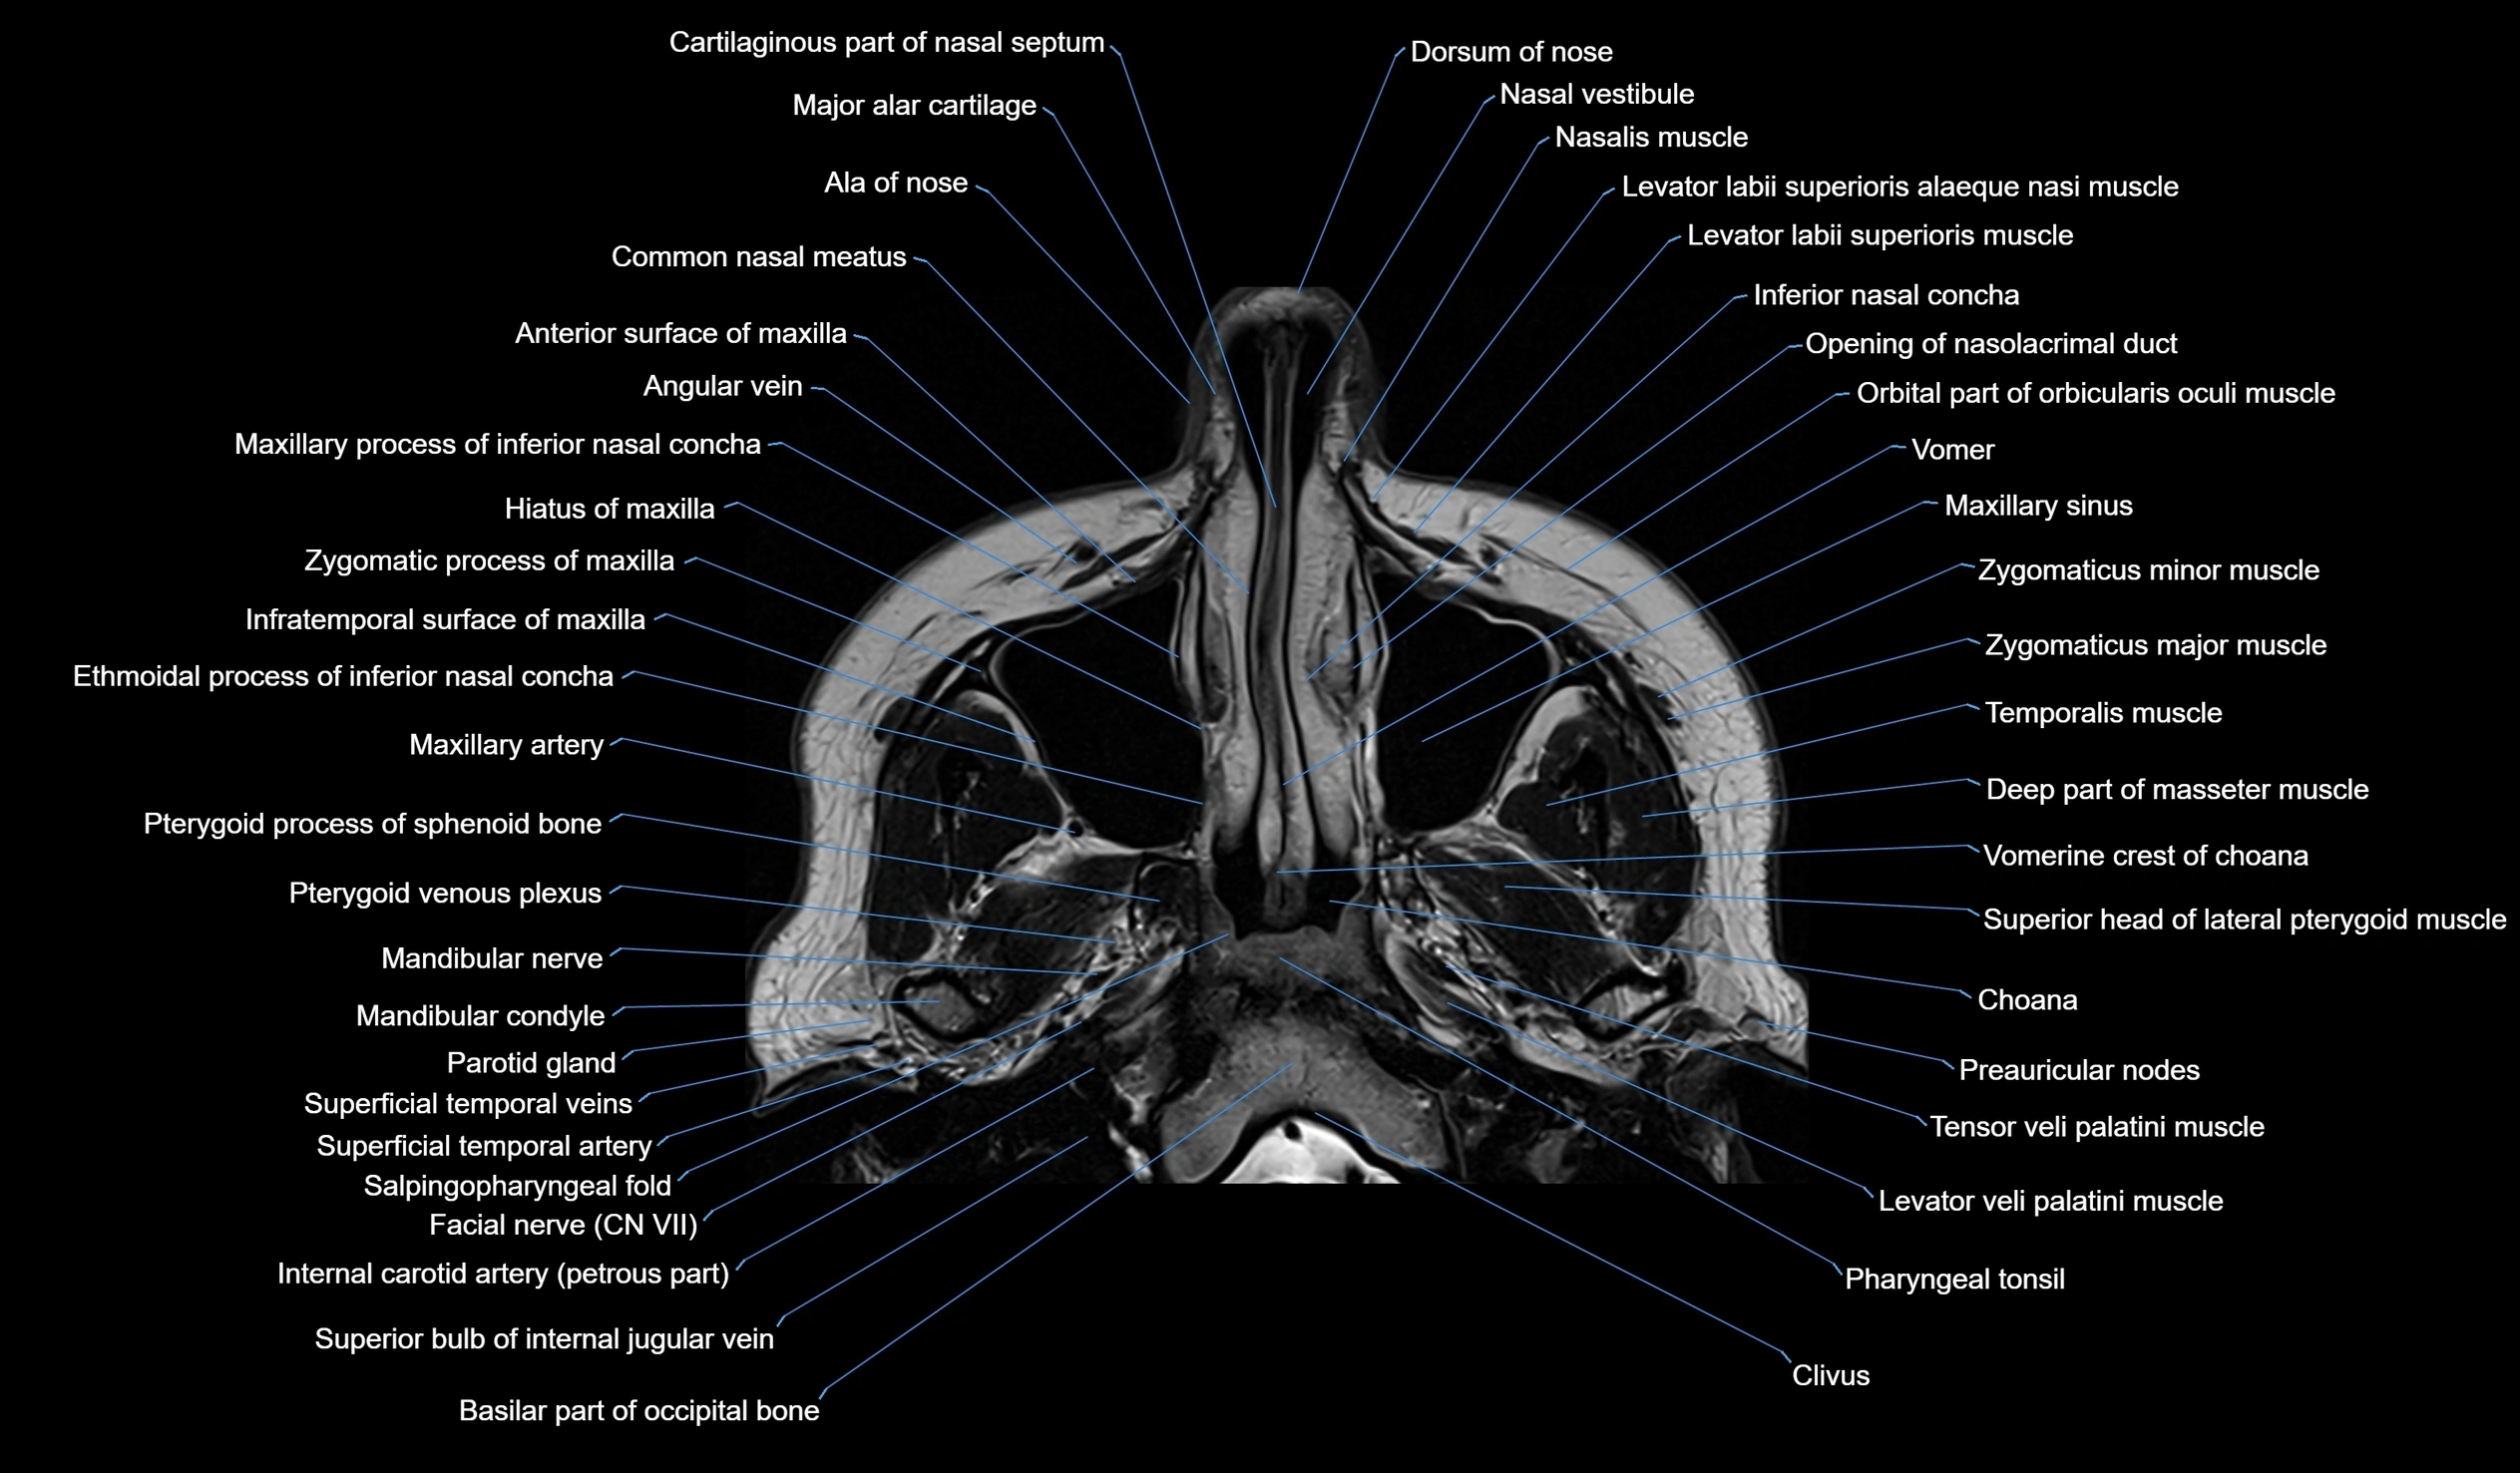

MRI images